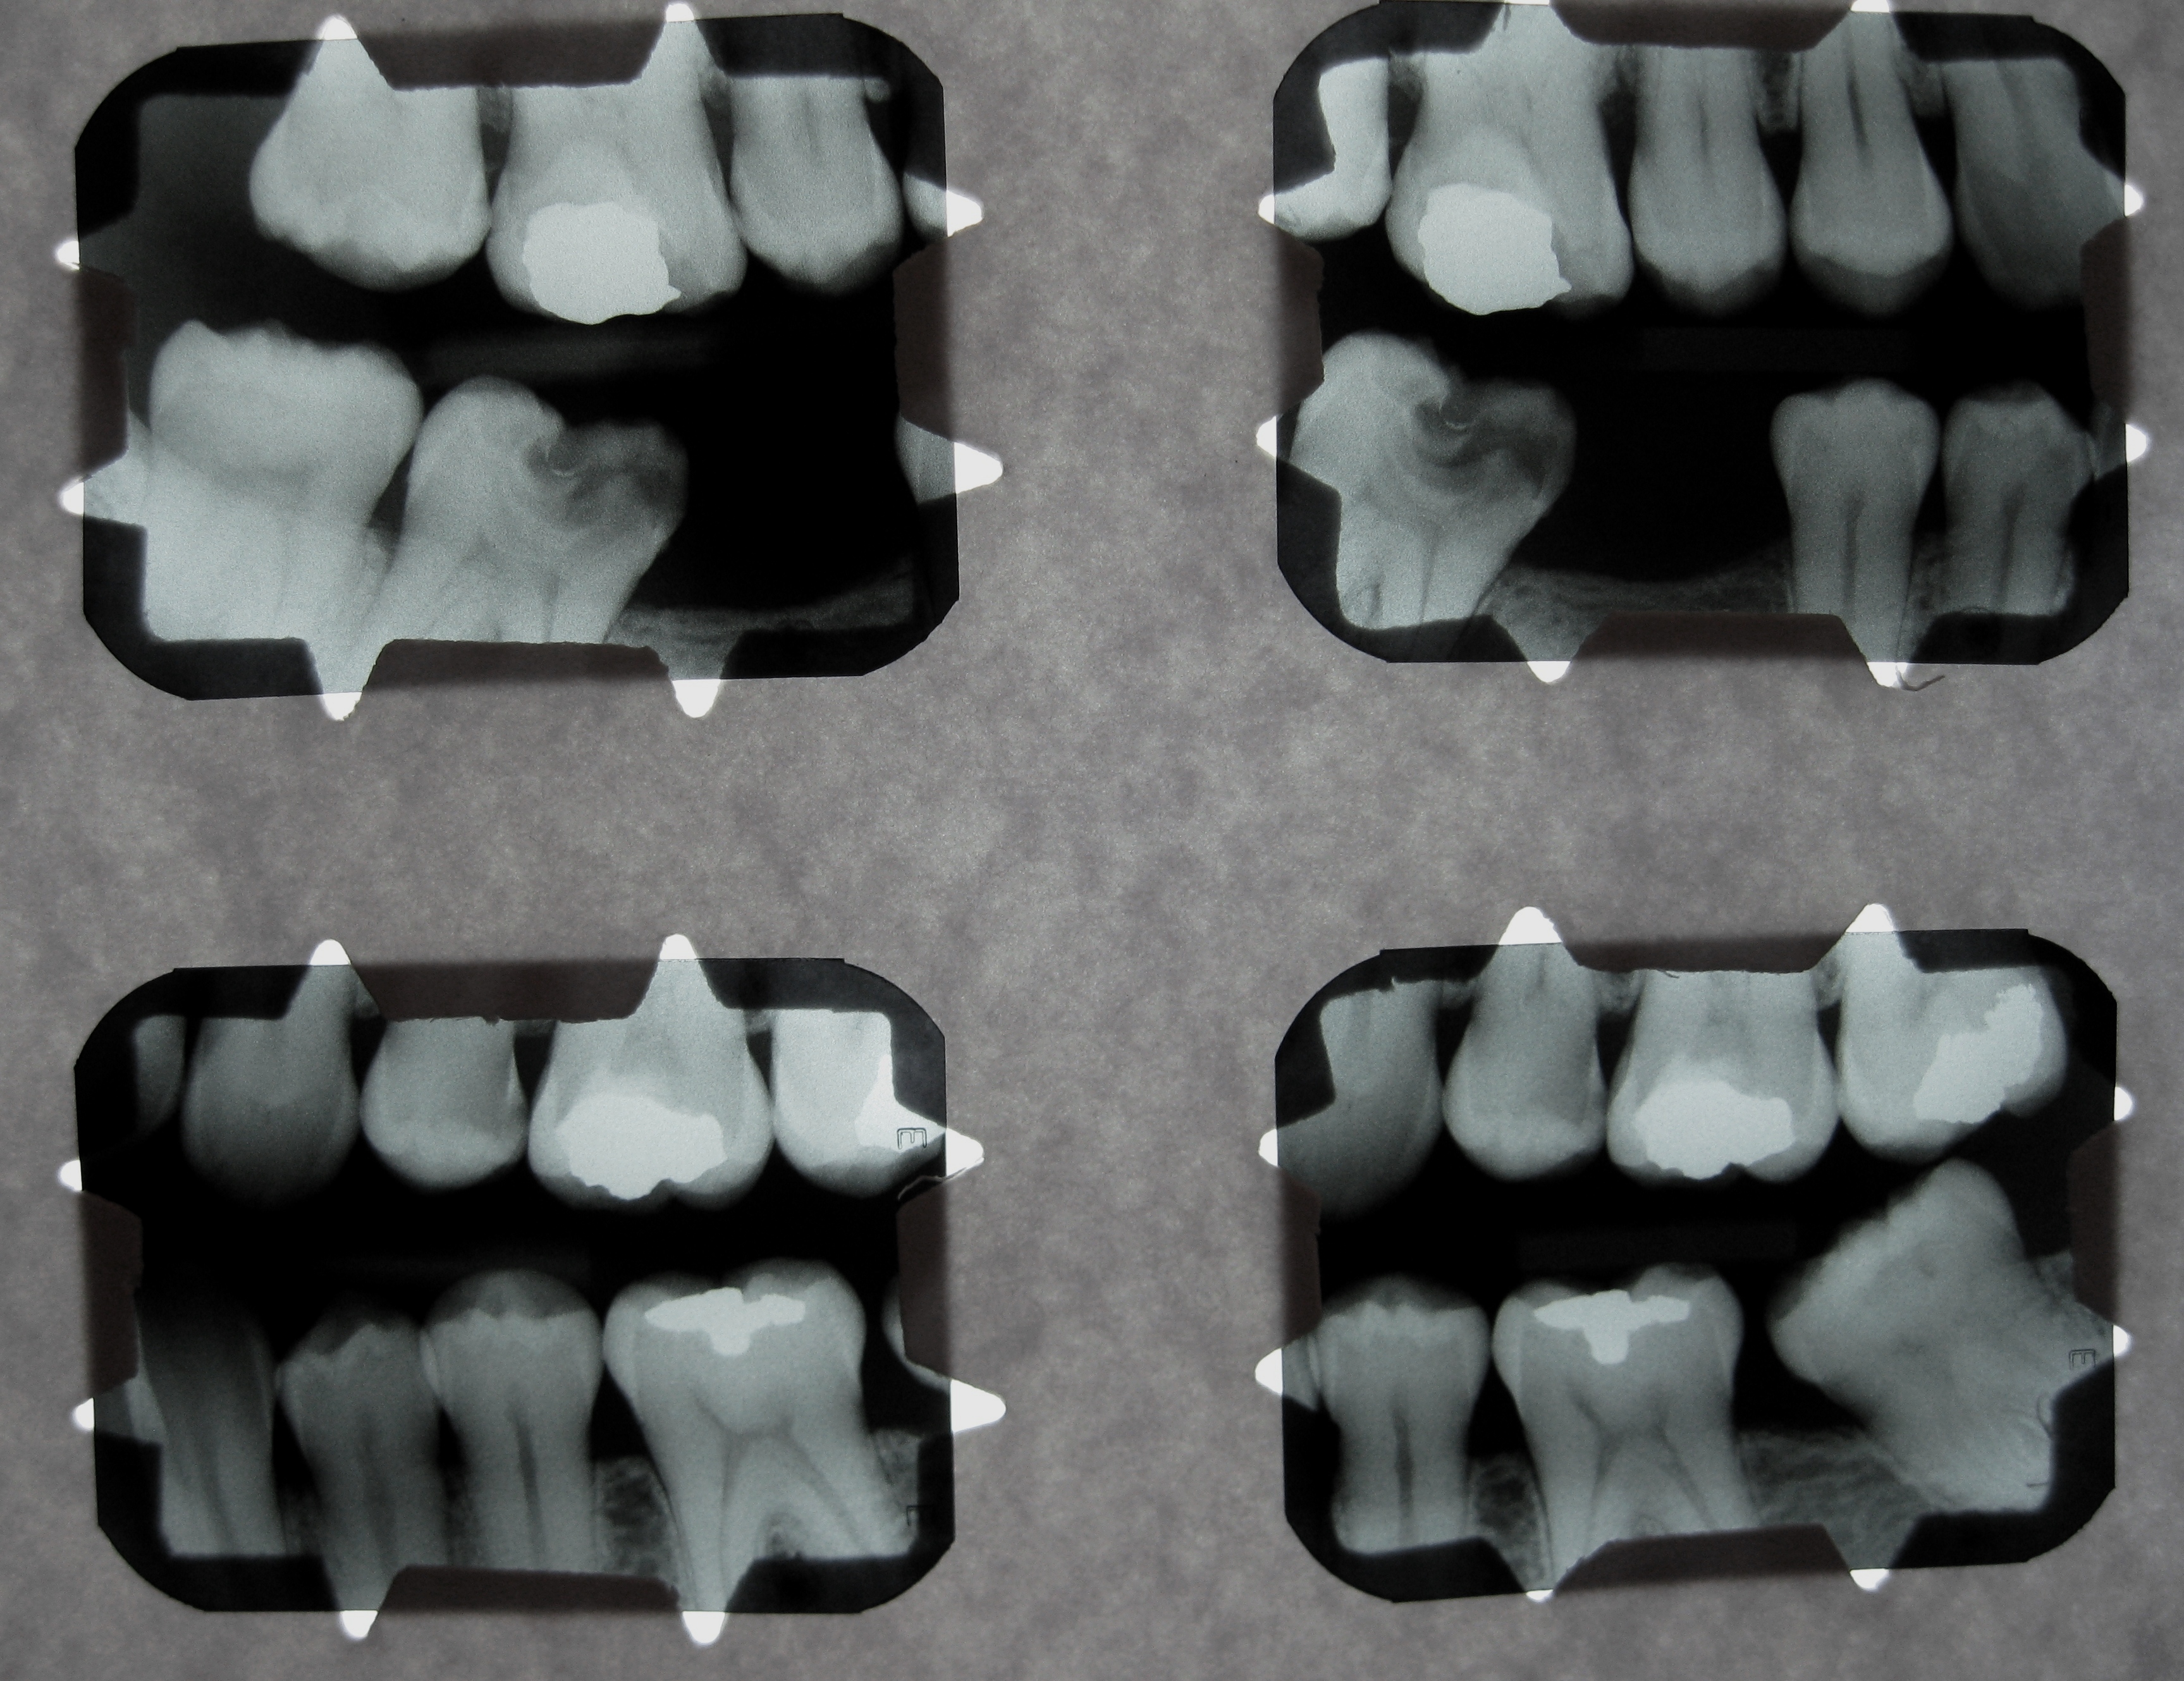

Debido a que trabajamos con la más avanzada tecnologia todas las radiografias digitales pueden ser entregadas/enviadas: Impresas en peliculas radiográficas con formato médico de alto contraste, CD y/o correo electrónico.